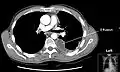

تصویر سیتی اسکن سینه که یک پلورال افیوژن را در سمت چپ نشان میدهد. مایع معمولاً بهدلیل نیروی گرانش در پائینترین فضای ممکن قرار میگیرد؛ در مورد این بیمار در پشت دیده میشود چرا که بیمار به پشت خوابیدهاست.